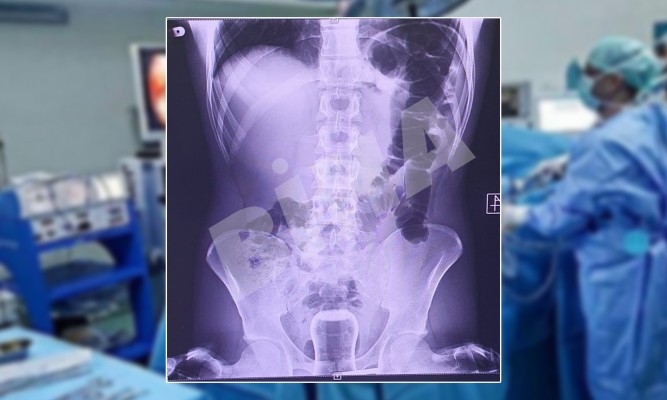

Dünya’da eşine az rastlanır bir olay Şanlıurfa’da yaşandı. Makatındaki sancı nedeniyle Mehmet Akif İnan Eğitim ve Araştırma Hastanesi’ne başvuran ismi öğrenilemeyen bir şahıs, muayene olduktan sonra röntgen çekimi için radyoloji bölümüne sevk edildi. Çekilen röntgende çıkan sonuç, görenleri hayrete düşürdü. Makatında çay bardağı görülen talihsiz adam, genel cerrahi servisinde ameliyata alındı.

Uzmanların yaptığı operasyonla makattaki çay bardağı, kırılmadan başarılı bir şekilde çıkarıldı. Ameliyatla eski sağlığına kavuşan şanssız adam, sağlık personeline olayla ilgili verdiği bilgide, hacamatçıya gittiğini ve yağlı bardağın kaza sonucu içine kaçtığını anlattığı öğrenildi. Şanlıurfa’da yaşanan bu skandal olay, uzun süre kamuoyunda konuşulacak gibi görünüyor.